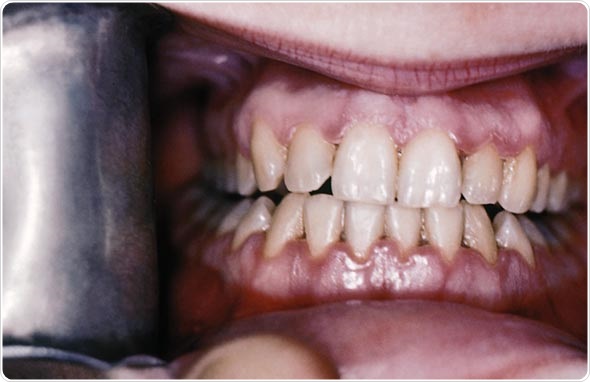

Toothache and gum swelling and pain are common symptoms. Gums may be red, tender to touch and recessing at the lower ends of the teeth. Teeth may also bleed on brushing.